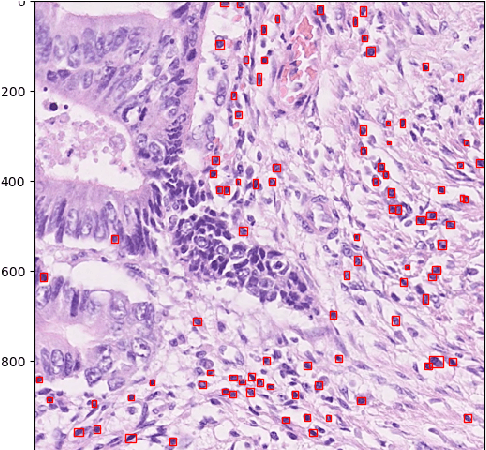

We consider the problem of counting cell nuclei from celltype-agnostic histopathological stains, exemplified here by the Haematoxylin and Eosin stain. We compare direct estimation by classification and regression against bounding box prediction models for a dataset with relatively low sample sizes. We find from a fine-grained analysis of MSE errors that all models suffer from a substantial underestimation bias. Detection models, while more capricious and sensitive in training, are more robust against underestimation in their optimum. Furthermore the simple idea of combining models from different prediction setups results in large improvements.